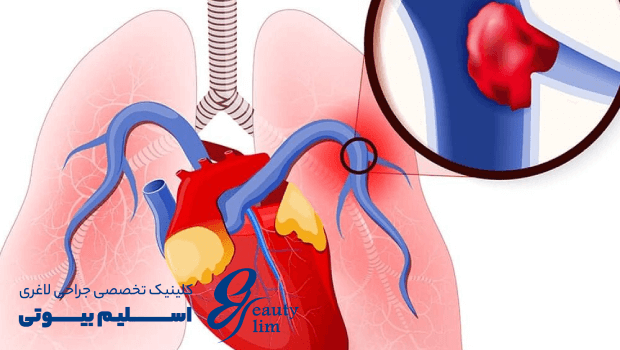

آمبولی یا لخته شدن خون در ریهها و سیستم گردش خون یکی از عوارض جدی پس از هر نوع جراحی است. بسیاری از بیماران نگران هستند که خطر آمبولی تا چه مدت پس از عمل وجود دارد و چگونه میتوان آن را شناسایی و پیشگیری کرد.

آمبولی زمانی رخ میدهد که لخته خون (ترومبوس) در رگها تشکیل شود و سپس به ریهها منتقل شود. این وضعیت میتواند تهدید کننده زندگی باشد و نیازمند تشخیص و درمان فوری است.